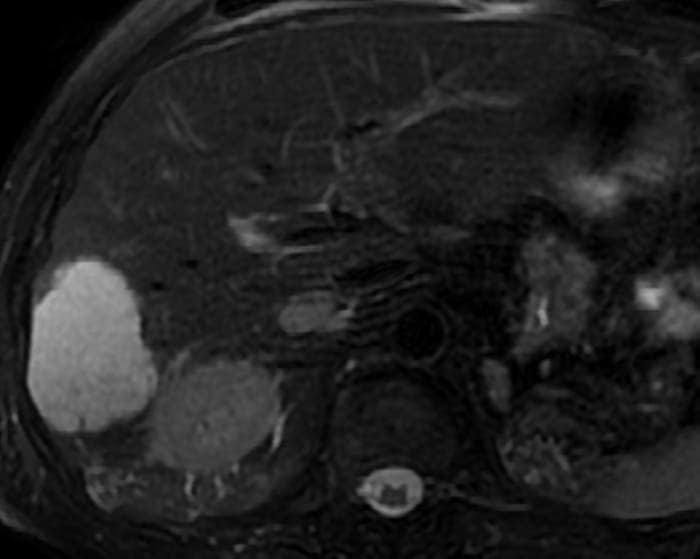

U máu gan

» Thông tin: Nam giới – 70 tuổi.

» Lâm sàng: Tiền sử ung thư thận.